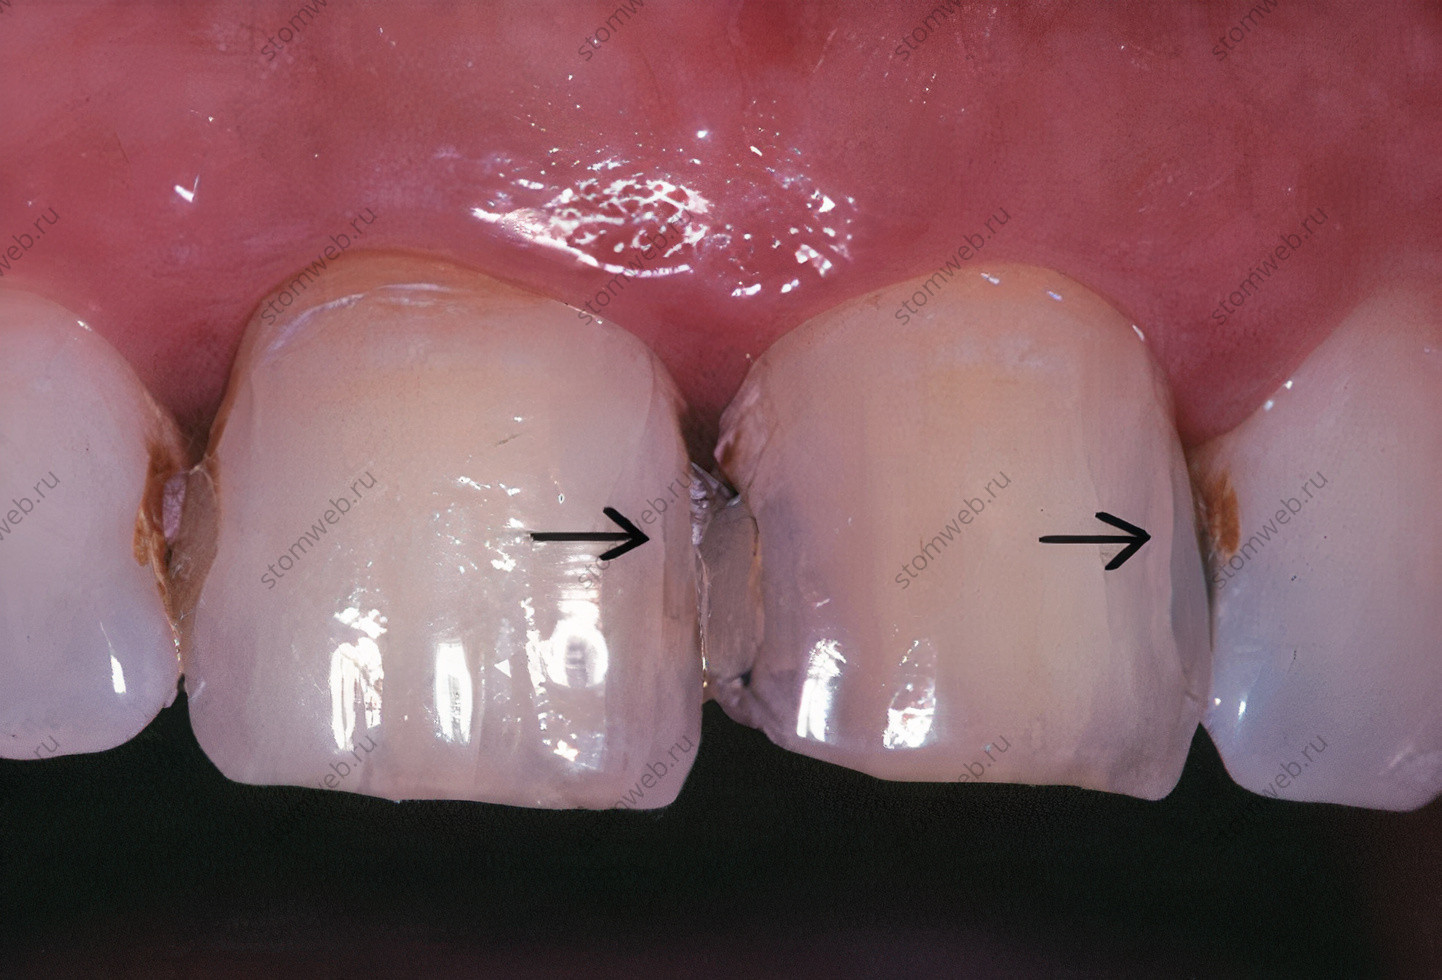

Два других термина представляют собой крайние значения переломов коронок. Линии трещин - это видимые трещины, затрагивающие только эмаль (рис. 5). Они могут распространяться на нижележащий дентин, но это обычно трудно определить. Они не связаны с симптомами, и лечение ведется по эстетическим показаниям. Другая крайность - это полный перелом зуба, который проходит через оба краевых гребня, обычно в мезио-дистальном направлении, полностью разделяя зуб на два отдельных сегмента (рис. 6). Для удобства в этой главе термин «перелом» обычно используется для различных переломов коронок.

Рисунок 5. Центральные резцы верхней челюсти с множеством трещин эмали (указано стрелками)